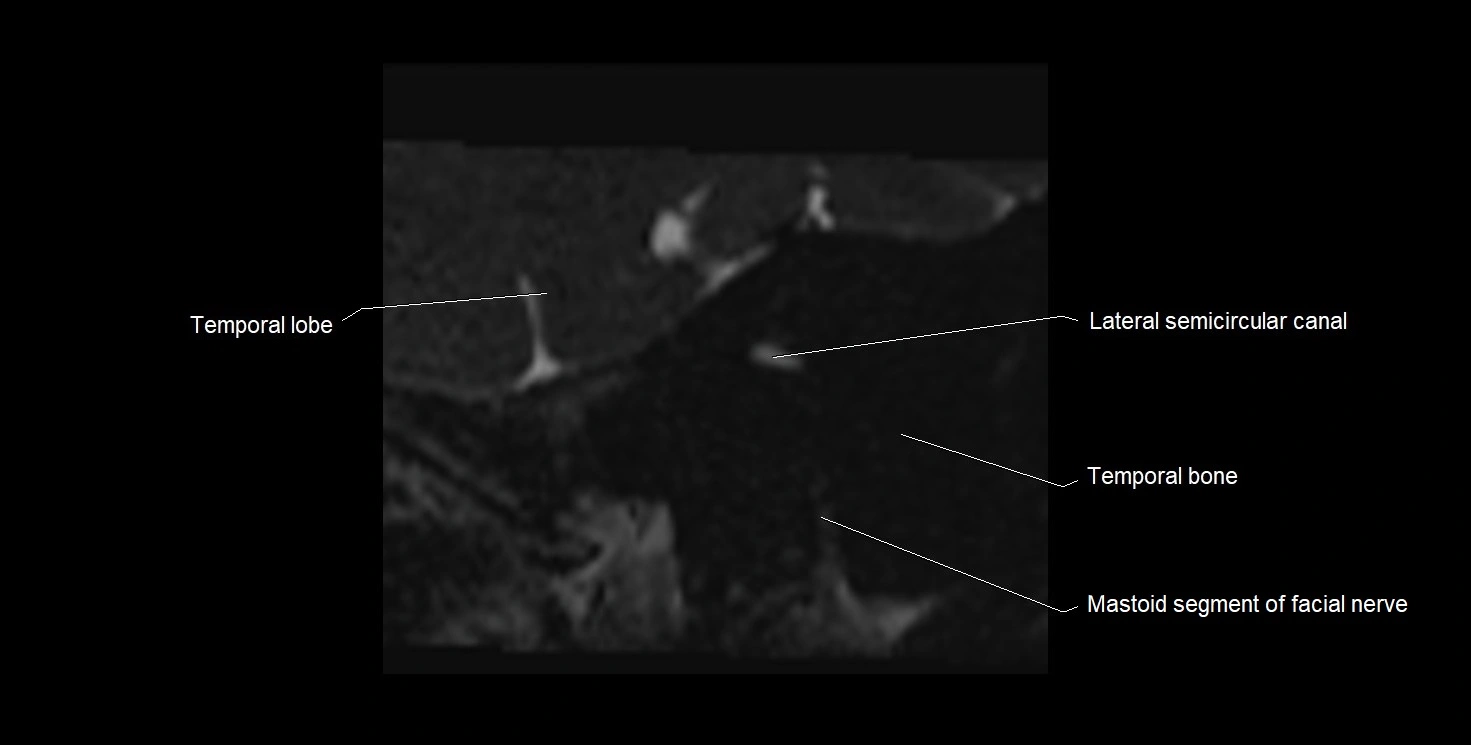

MRI images

image